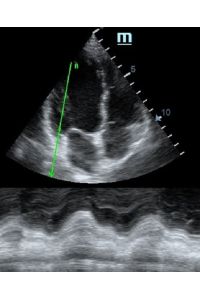

Но как же провести стандартные измерения в М-режиме, если мы его не использовали? На помощь приходит функция Free Xros M – анатомический М-режим. Имея записанную в память прибора видео петлю, мы можем провести линию М-режима в любом месте, при этом корректируя изначально не оптимальный угол.

Оценка сокращения сегментов левого желудочка на глаз постепенно уходит в прошлое. Если в приборе нет функции радиального или лонгитудинального стрейна, на помощь опять может прийти Free Xros. Утолщение более 5 мм в систолу – нормальное сокращение, 2-5 мм гипокинез, истончение в систолу – дискинез.